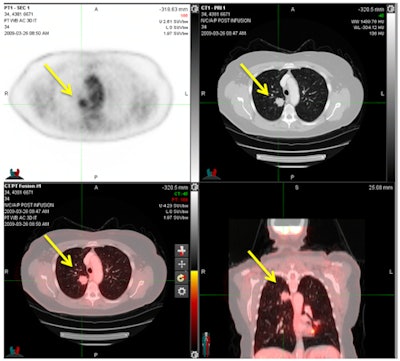

CHICAGO - With high specificity and negative predictive value, FDG-PET/CT can accurately detect distant metastases in women with cervical or endometrial cancer and spare them from unnecessary aggressive therapy, according to a study presented on Sunday at RSNA 2016.

FDG-PET/CT also achieved a false-positive rate of less than 5%, prompting researchers to recommend that the hybrid modality be included as part of pretreatment evaluation for this patient population.

FDG-PET/CT revealed distant metastases in 21 (13.7%) of the cervical cancer patients and in 24 (11.8%) of the endometrial cancer patients. The most common locations for distant metastases among women with cervical cancer were the lungs (5.2%) and the peritoneum (4.6%). Among the endometrial cancer patients, the peritoneum (6.4%) was the most common site for distant metastases.

"In summary, greater than 10% of advanced cervical and high-risk endometrial cancer patients have unsuspected distant metastases at the time of presentation," Gee told RSNA attendees. "FDG-PET/CT demonstrates high accuracy and negative predictive value for distant metastases, and we believe it should be included in the staging evaluation of these patients."